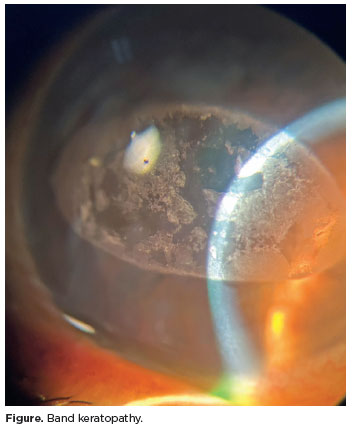

Band keratopathy (Figure) is a degenerative disease localized in the interpalpebral aperture(1). It consists of band-shaped fine calcium deposits in the anterior corneal layers(2). Its mechanism is unknown(1). Early stages are asymptomatic(2); however, over time, common complaints include a sensation of a foreign body in the eye, lachrymation, photophobia, visual acuity deterioration, and glare(1). Treatment aims to restore corneal surface, including mechanical debridement, superficial keratectomy, ethylenediaminetetraacetic acid chelation, and phototherapeutic keratectomy(2).